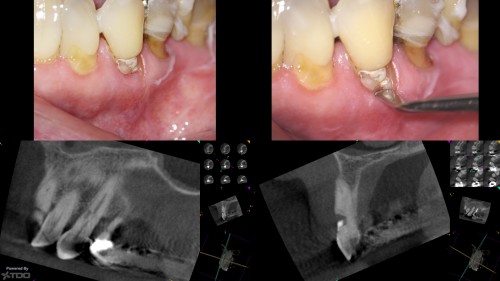

External Cervical Resorption

By Carlos Aznar Portoles / September 7, 2018